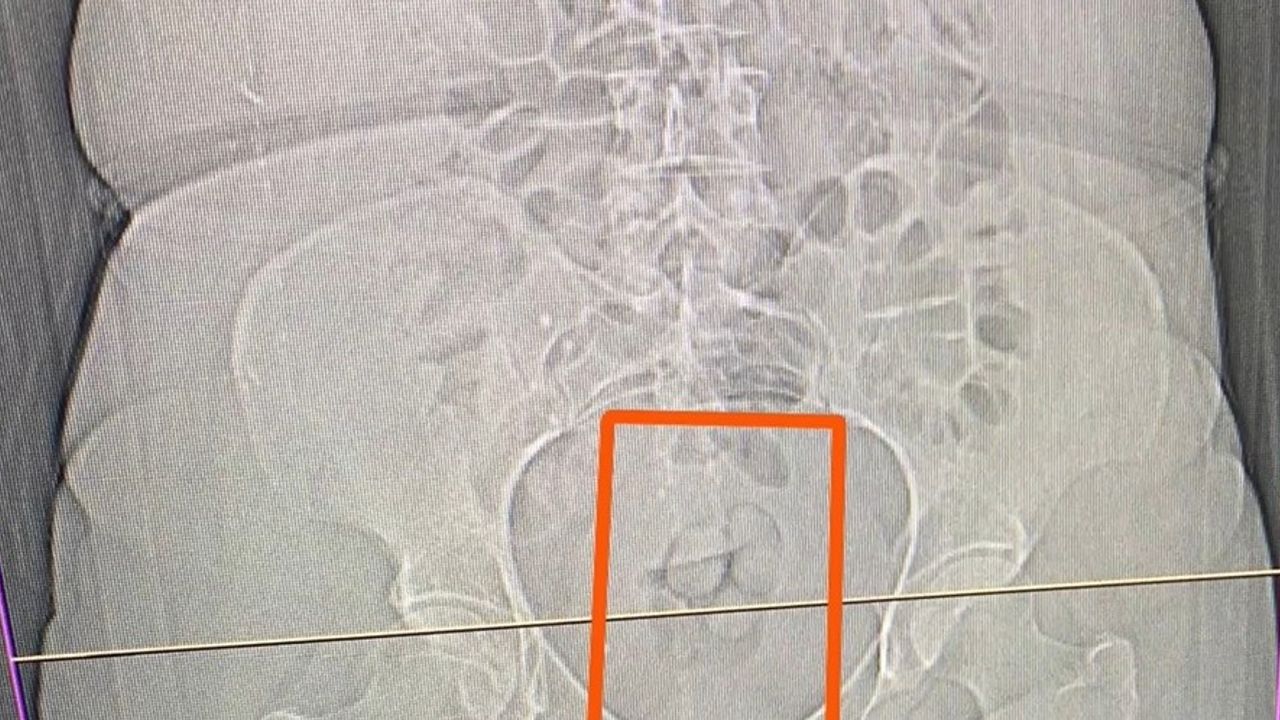

S.S. isimli şahısın şüpheli görülmesi üzerine çekilen tomografi neticesinde şahsın midesinde yabancı maddeler tespit edildi. Yapılan iç beden muayenesi sonucunda ise şahıstan 21,39 gram metamfetamin maddesi ele geçirildi.